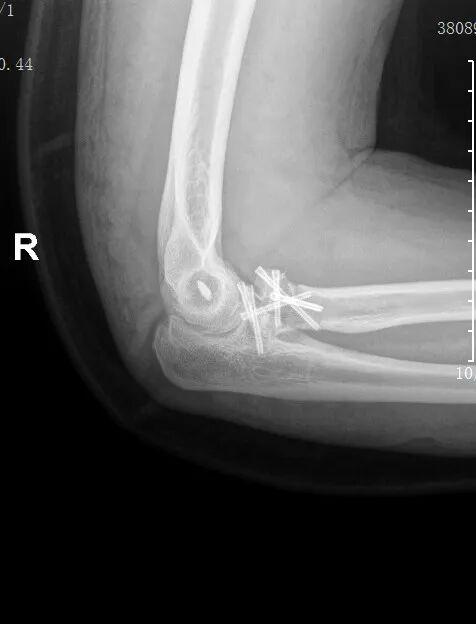

术后复查提示:骨折对位对线良好,内固定位置理想。目前,郑先生正在医护团队的专业指导下开展循序渐进的康复训练,肘部功能逐步恢复,预后良好。

患者术后复查影像